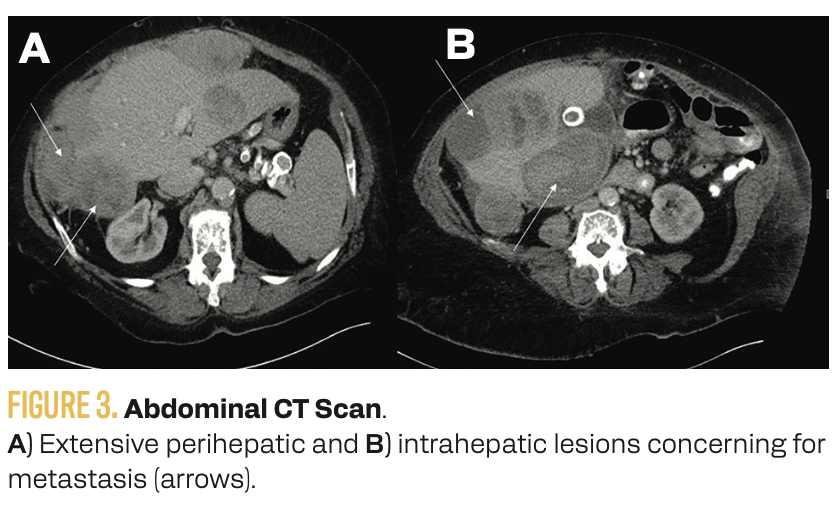

On physical examination, a palpable mass was noted in the midabdomen, extending to the right upper quadrant. Complete blood count and comprehensive metabolic panel were unremarkable. An abdominal ultrasound revealed a solid mass with cystic lesions within the liver (Figure 2). An abdominal CT scan demonstrated extensive perihepatic and intrahepatic lesions suggestive of metastasis (Figure 3). A colonoscopy showed only diverticular disease, and a bilateral screening mammogram result was normal.

FIGURE 3. Abdominal CT Scan.